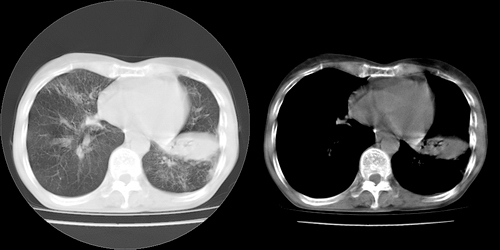

以下是引用lihuuuu在2006-7-18 18:16:00的发言:[br]支持肺结核诊断[br]本病例符合结核“三多”“三少”特征(多病灶、多形态、多钙化、少肿块、少堆积、少增强)中的前五个特征,另外左下叶背段有不张样改变-考虑伴有支气管内膜结核所致段不张。

以下是引用yang4132在2006-7-18 10:04:00的发言:[br]两肺多发 多形态病变,部分半纤维条索和斑点壮钙化,胸膜肥厚粘连,考虑结核。